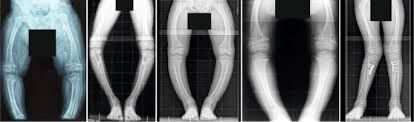

X-Linked Hypophosphatemia Market Analysis and Forecast to 2028

The increased focus in the development of therapeutic treatment for rare disorders affecting the global population will be the key driving factor for the growth of this market. Advanced technologies enabling better research and collaboration between the scientists and pharmaceutical communities in inventing new drugs like burosumob will further propel the market growth. Significant increase in early detection and treatment of genetic disorders in children will be a market booster. Covid-19 pandemic will have minimal impact on this market since XLH is not a viral infection. The main challenges hampering the growth of this market are counterfeit drugs, lack of awareness and complications linked with post-operative care.

The entire x-linked hypophosphatemia market has been sub-categorized into treatment and end-user. The report provides an analysis of these subsets with respect to the geographical segmentation. This research study will keep marketer informed and helps to identify the target demographics for a product or service.

• Surgical or Orthopedic Treatment